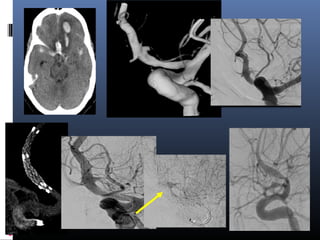

Dissections with blister

EVD

2-overlapping Enterprise stents

A B C

D E F

Very small aneurysms …

Dissecting

blister

aneurysm –

poor grade